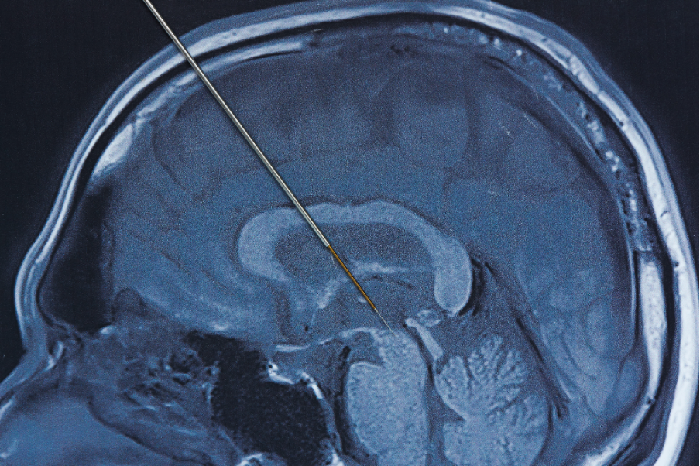

Mengenal Deep Brain Stimulation, Prosedur untuk Bantu Kendalikan Parkinson